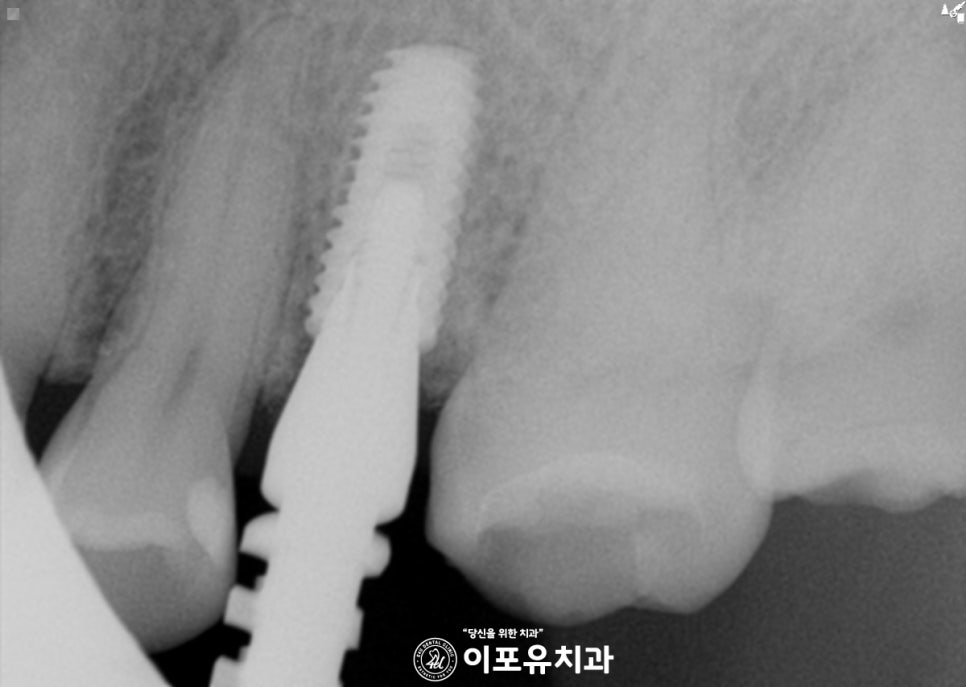

다행히 안적적으로 심어져 있는 모습이네요.

골 유착이 확인된 뒤에 코핑 체결을 통해

보철 제작을 진행하게 됩니다.